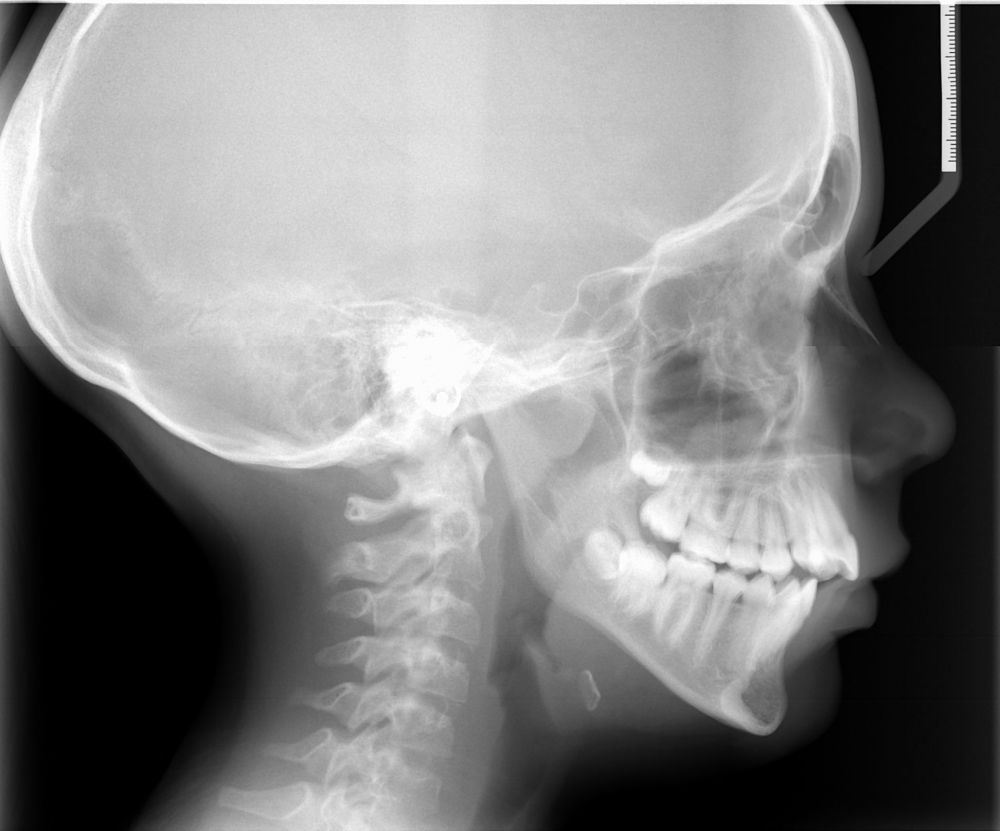

La respiration

La respiration se faisant par le nez, il est normal que la langue reste à l'intérieure de la bouche. Chez certaines personnes, la respiration est dite buccale. Ce sont souvent des personnes atteintes d'obstruction nasale (nez bouché). L'enfant respire la bouche ouverte.

Education fonctionnelle

Pour une bonne croissance, il est indispensable que les fonctions (respiration, déglutition, mastication, phonation et posture) soient correctes. C'est le rôle de l'éducation fonctionnelle.